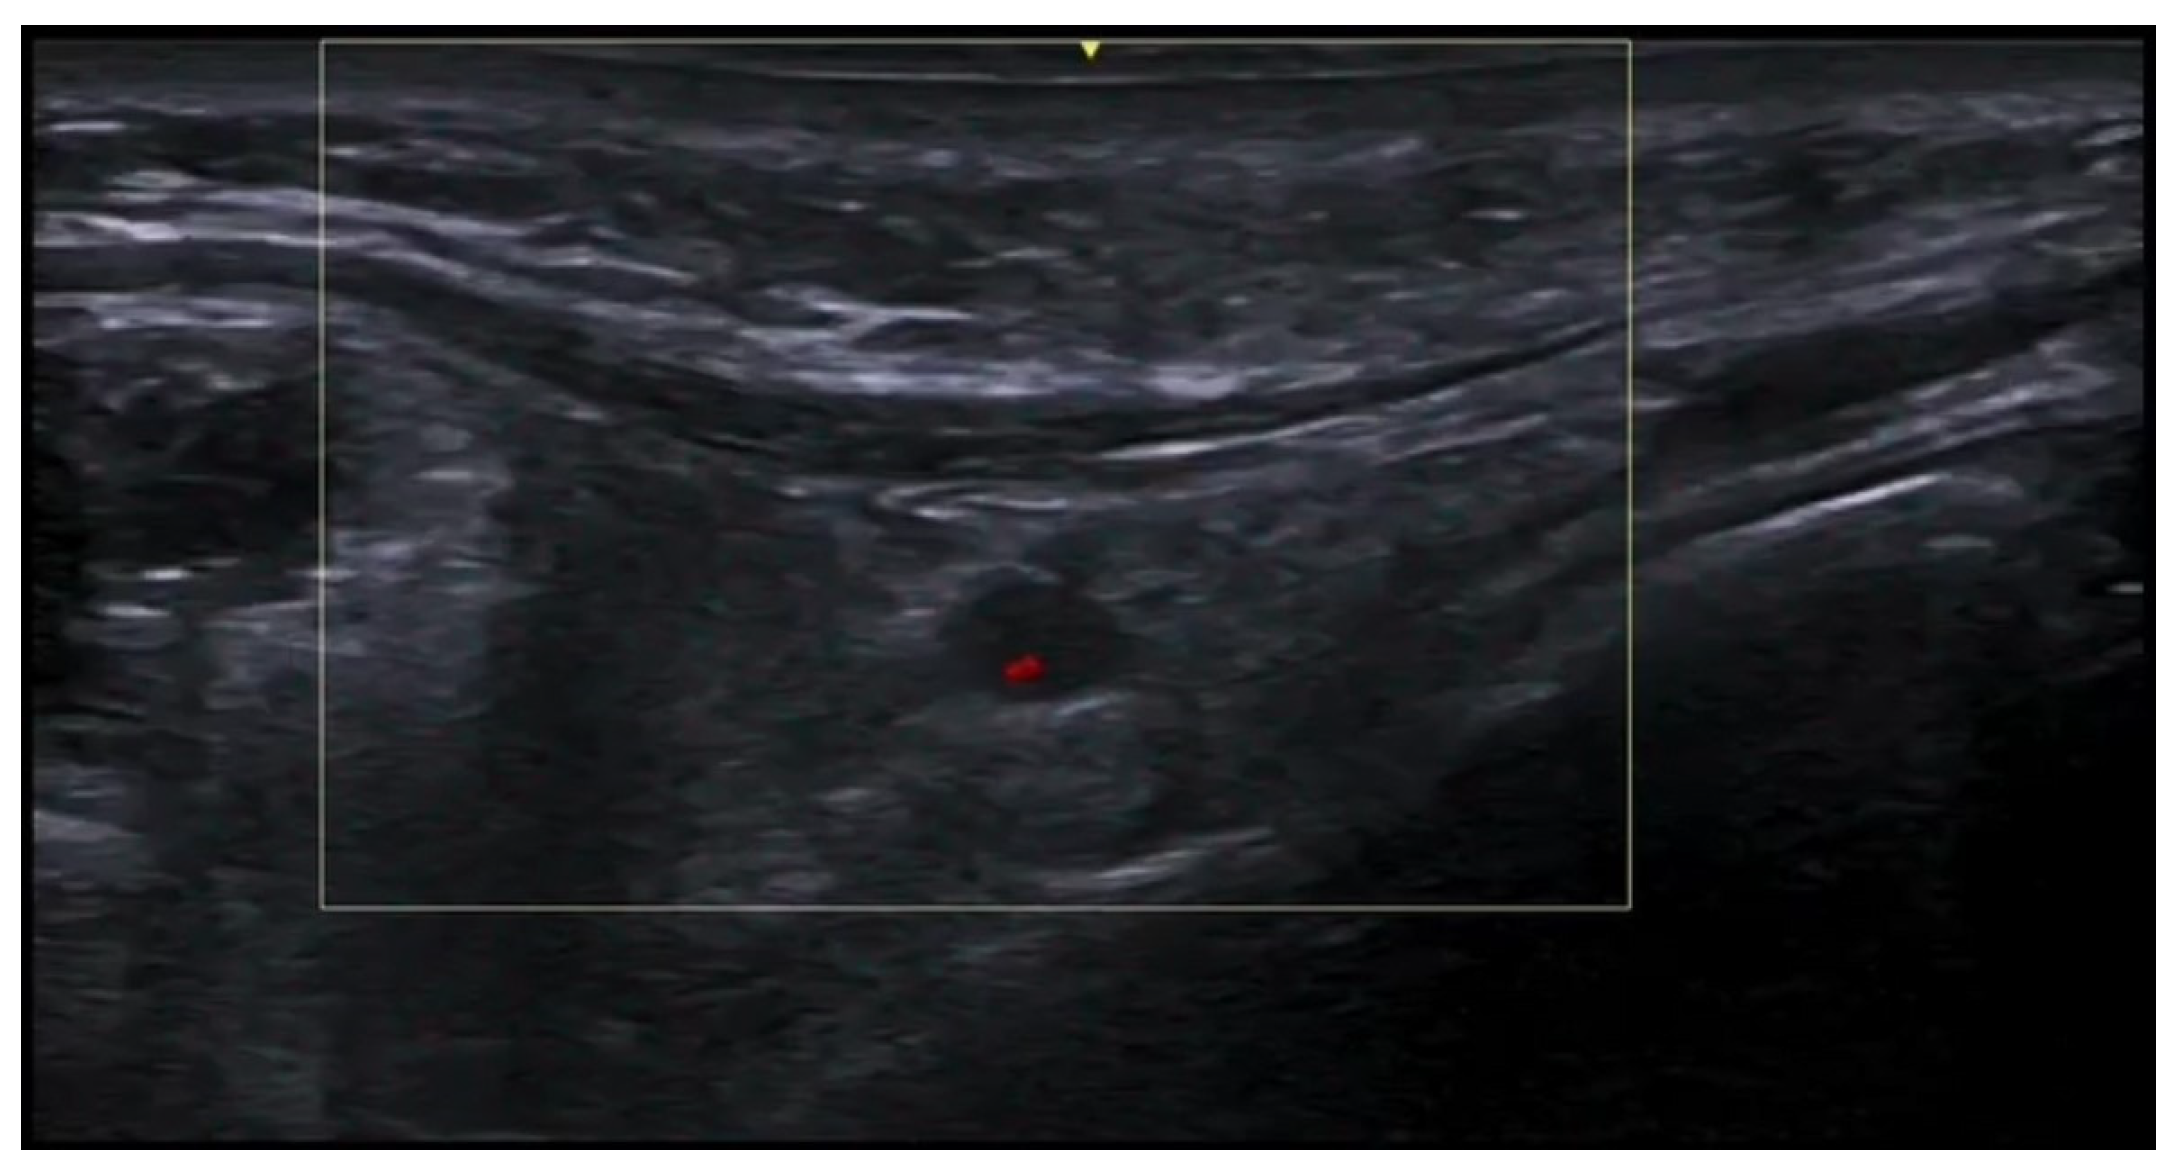

- Di Battista, M.; Vitali, S.; Barsotti, S.; Granieri, G.; Aringhieri, G.; Morganti, R.; Dini, V.; Della Rossa, A.; Romanelli, M.; Neri, E.; et al. Ultra-high frequency ultrasound for digital arteries: Improving the characterization of vasculopathy in systemic sclerosis. Semin. Arthritis Rheum. 2022, 57, 152105. [Google Scholar] [CrossRef] [PubMed]